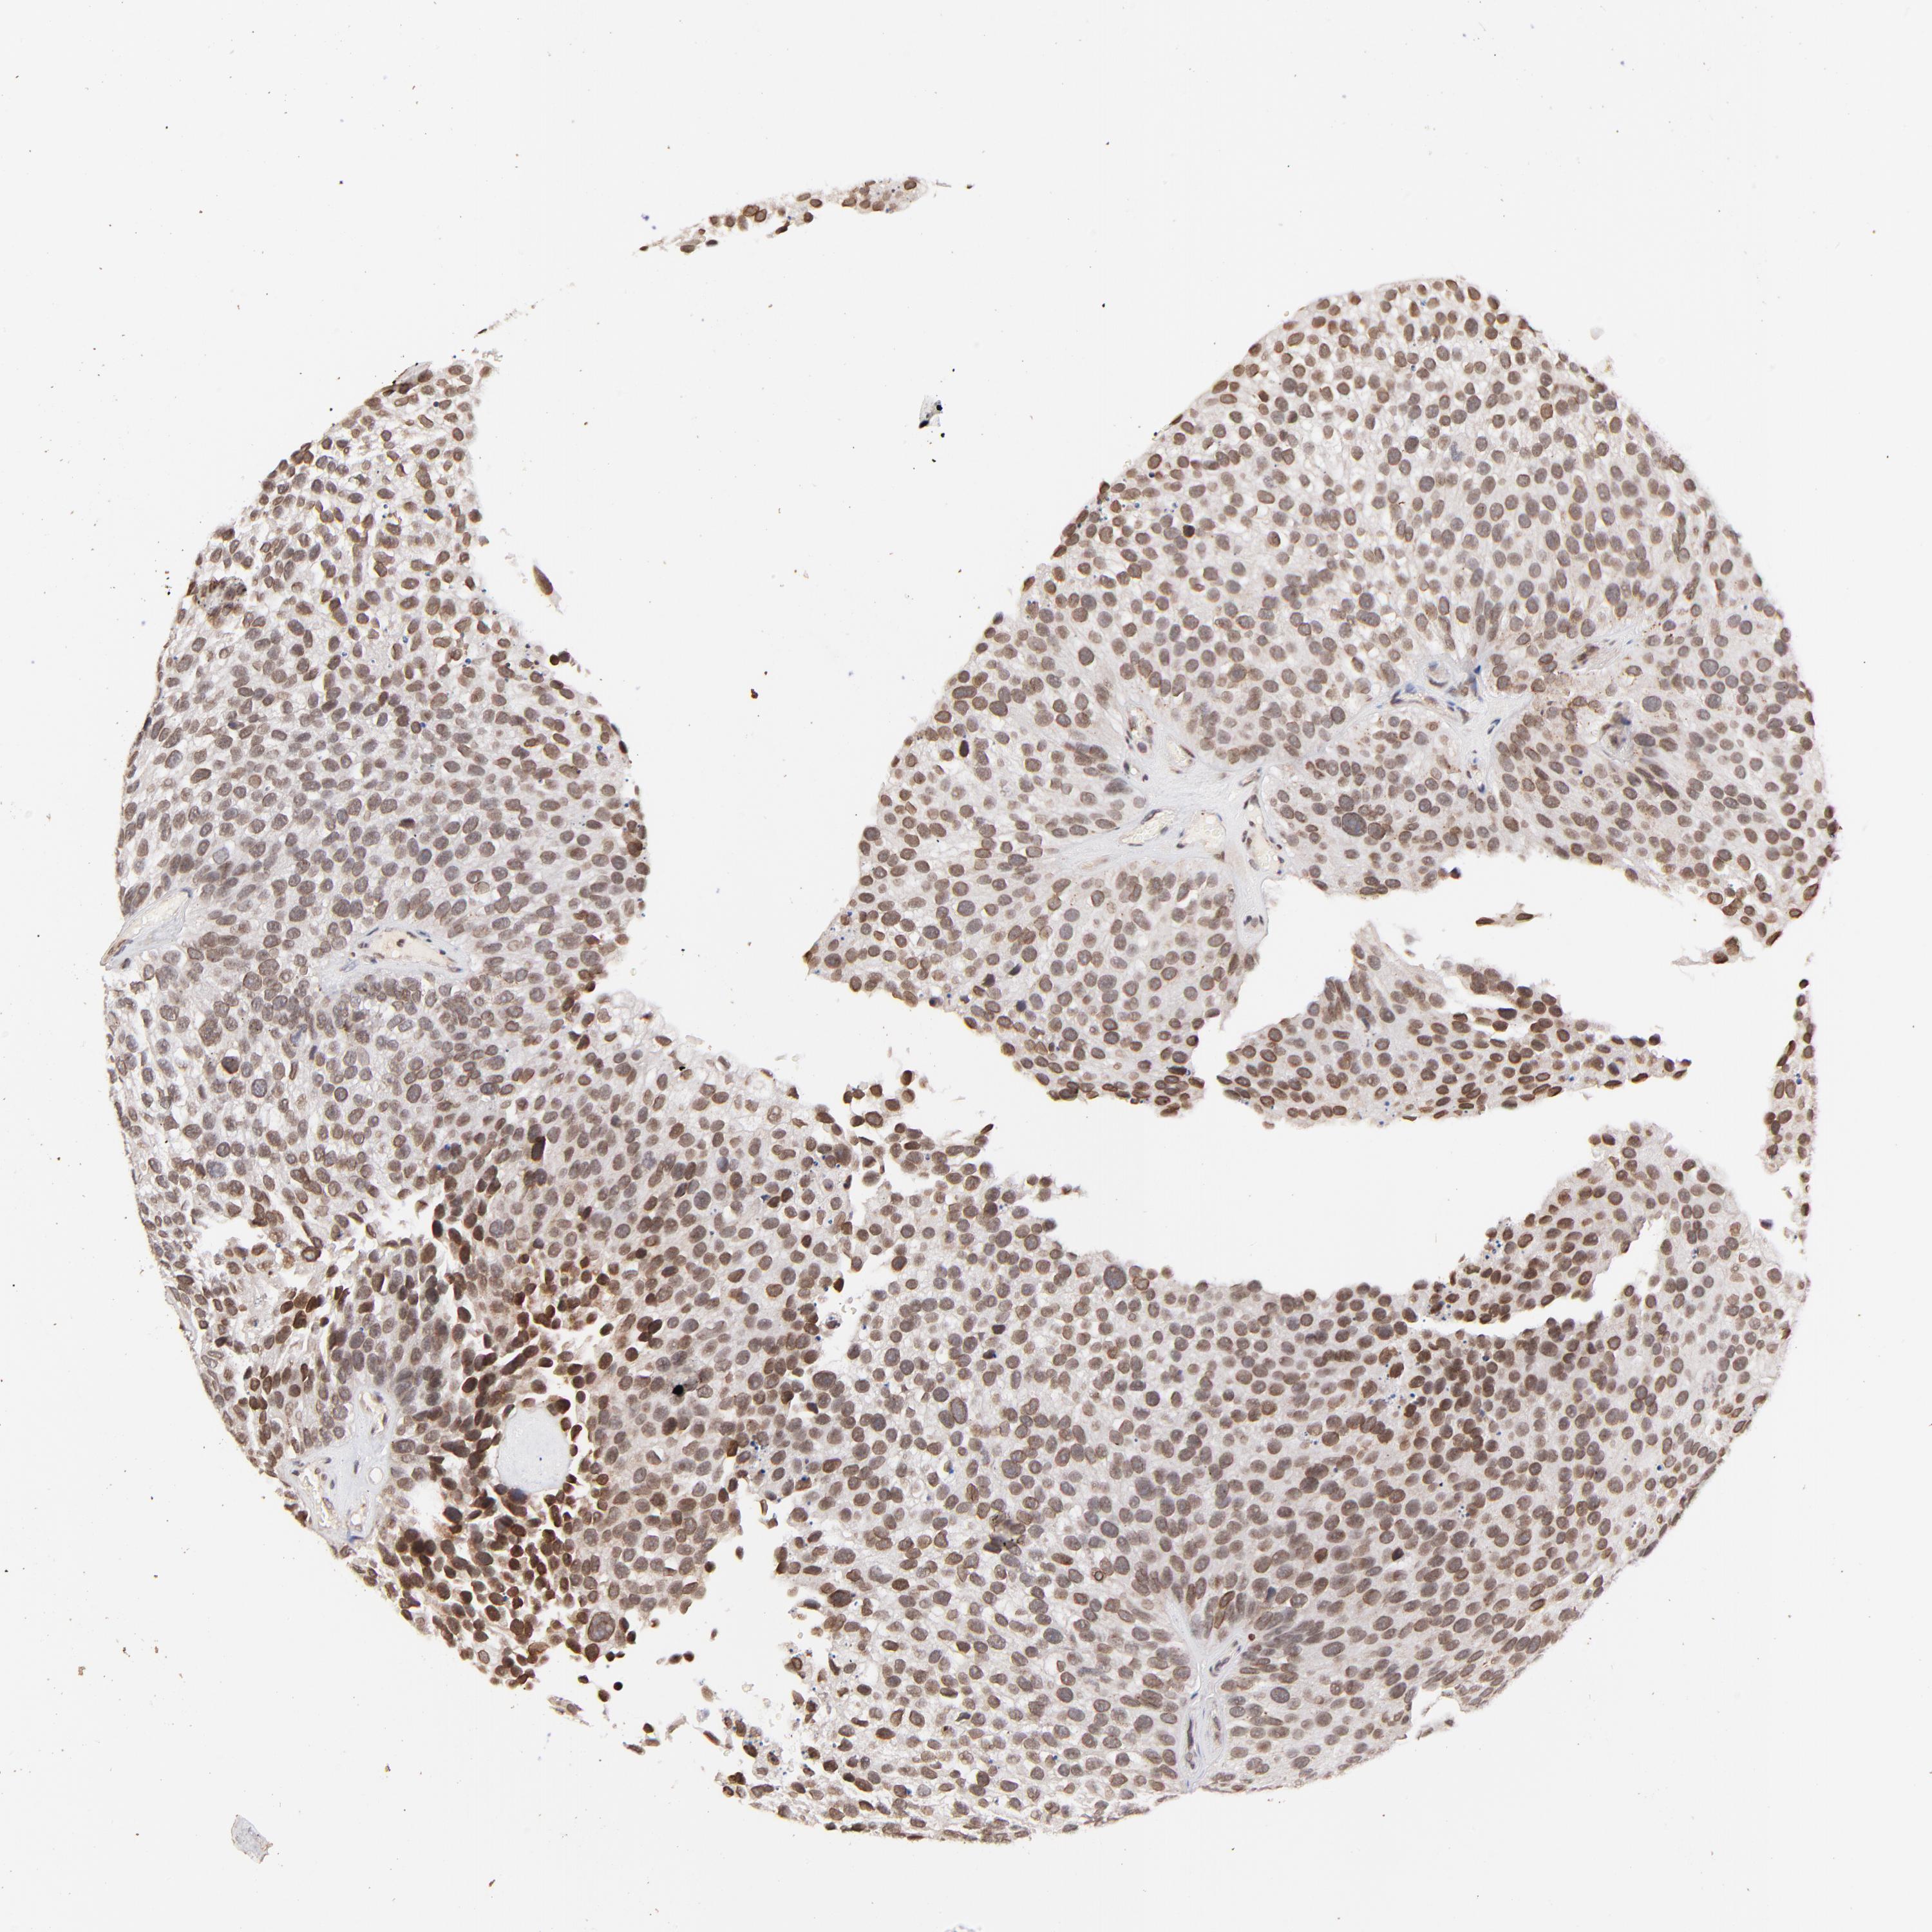

UROTHELIAL CANCER - Protein expressioni

A mouse-over function shows sample information and annotation data. Click on an image to view it in a full screen mode. Samples can be filtered based on level of antibody staining by selecting one or several of the following categories: high, medium, low and not detected. The assay and annotation is described here.

Note that samples used for immunohistochemistry by the Human Protein Atlas do not correspond to samples in the TCGA dataset.

Antibody stainingi

Antibody staining in the annotated cell types in the current human tissue is reported as not detected, low, medium, or high, based on conventional immunohistochemistry profiling in selected tissues. This score is based on the combination of the staining intensity and fraction of stained cells.

Each image is clickable and will lead to virtual microscopy that enables deeper exploration of all samples and also displays staining intensity scores, fraction scores and subcellular localization as well as patient and tissue information for each sample.

Antibody HPA003030

Staining

High

Medium

Low

Not detected

Intensity

Strong

Moderate

Weak

Negative

Quantity

>75%

75%-25%

<25%

None

Location

Nuclear

Cytoplasmic/membranous

Cytoplasmic/membranous,nuclear

Urothelial carcinoma, High grade

Urothelial carcinoma, Low grade

Adenocarcinoma, NOS